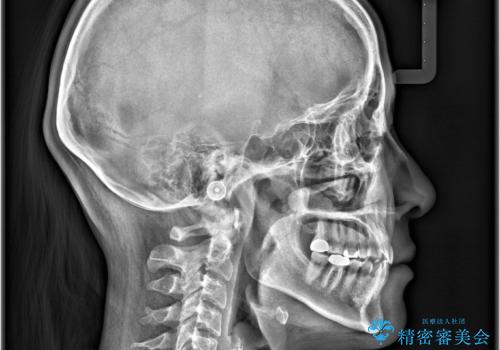

- すきっ歯と切端咬合(上下の前歯が先端で当たるかみ合わせ)を主訴にご来院された患者様です。

矯正検査を行った結果、非抜歯でインビザラインによる治療が可能と判断し、マウスピース矯正で改善を行いました。